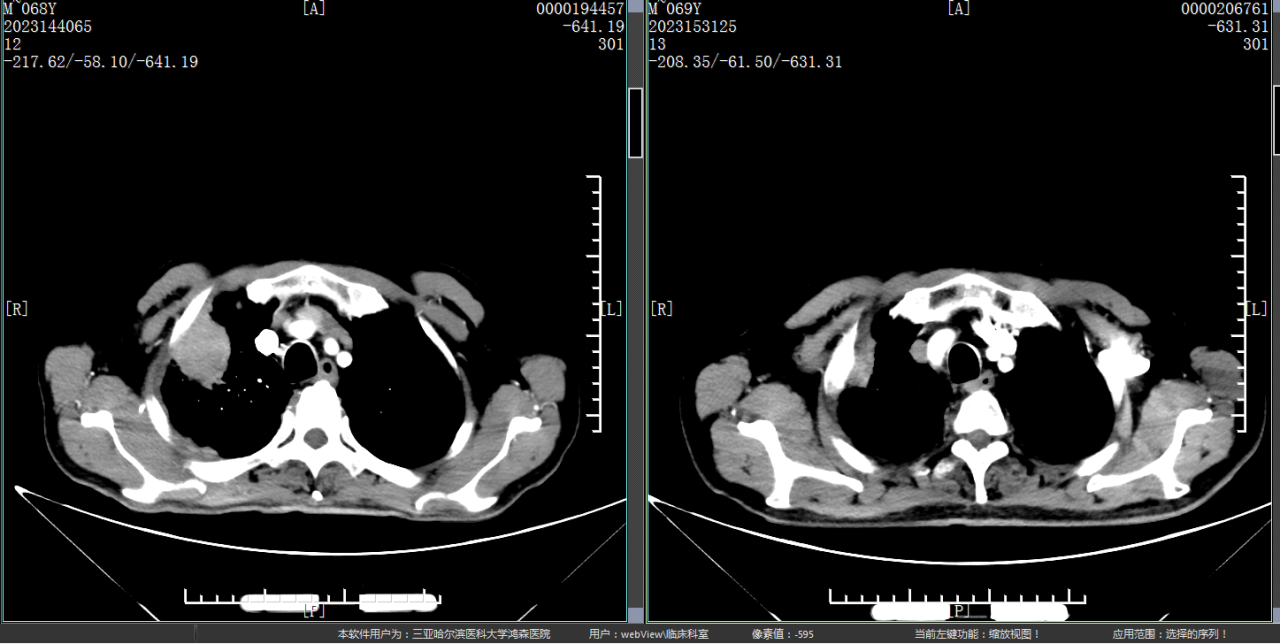

为明确肿块性质,更好地制定下一步治疗计划,经肿瘤科李玉成主任与放射影像中心王强主任研究讨论,决定行CT引导下精准定位肺部穿刺活检术。患者与家属极度焦虑与恐惧,在李玉成主任与患者及家属反复、耐心讲解此类病症的诊治及相关知识,通过沟通、安抚其情绪,取得患者及家属同意后,于5月30日在CT引导下行肺占位穿刺活检。 ▲在CT引导下行肺占位穿刺活检术 放射影像中心王强主任与肿瘤科李玉成主任共同制定了全面的操作方案,在技术组技师密切配合下,确定肺肿瘤穿刺定位,李玉成主任按照技术操作规范顺利完成穿刺活检。术后病理提示肺腺癌,基因检测为EGFR及ALK等驱动基因阴性结果。 ▲患者治疗前与治疗4周期后对比